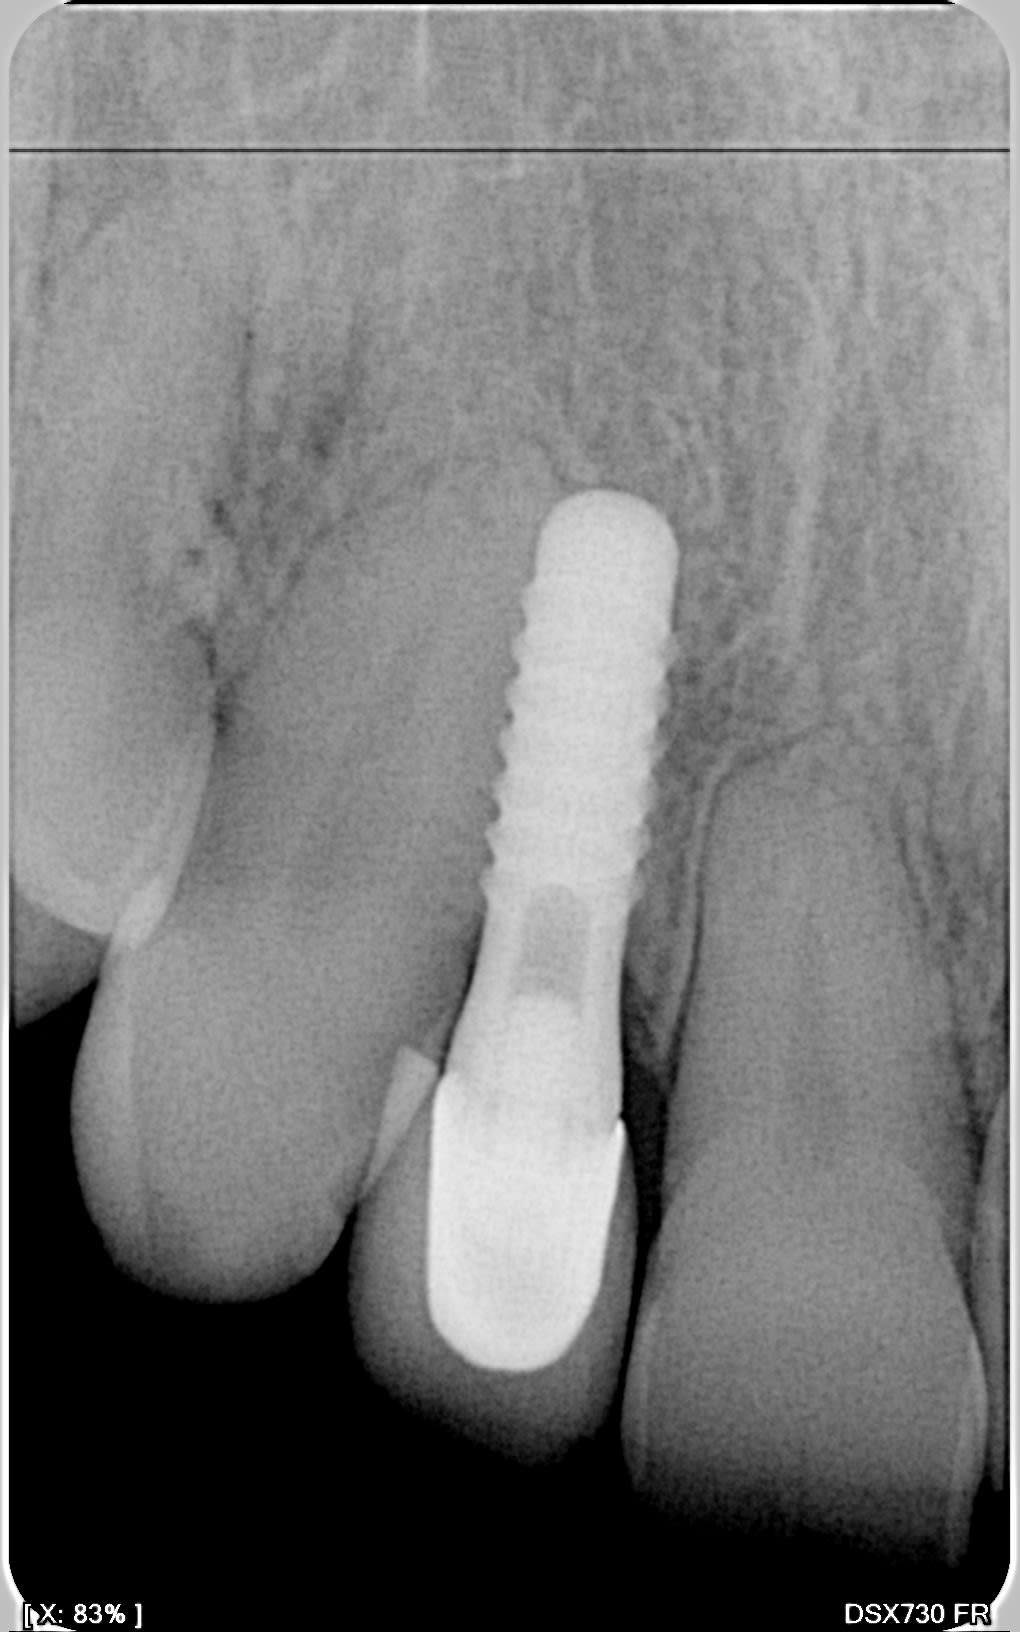

Je recherche à identifier ces implants posés il y une vingtaine d'années.

Mesures sur la radio diamètre 3 entre les spires et plateforme 4 mm.

La patiente me parle de Straumann mais d'après la société les dimensions ne correspondent pas à leur catalogue.

Sur la première radio on voit un espèce/ancêtre de synocta.

sûr et certain, c'est du Straumann...

C'est ce que je pensais mais Straumann dit le contraire, d'après eux , ces dimensions d'implants ne sont pas et n'ont jamais été dans leur catalogue.

"Mesure sur la radio" -> tes mesures sont fausses

C'est du straumann 100% sûr